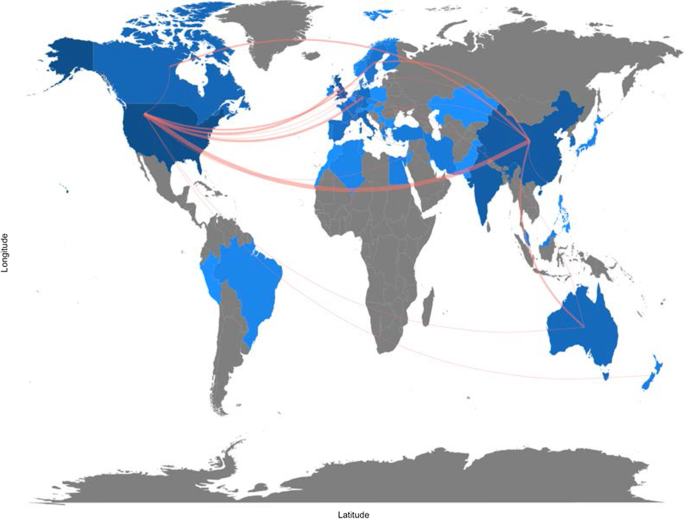

The investigation showed that the literature in this field is emerging. It focuses on health services management, predictive medicine, patient data and diagnostics, and clinical decision-making. The United States, China, and the United Kingdom contributed the highest number of studies. Keyword analysis revealed that AI can support physicians in making a diagnosis, predicting the spread of diseases and customising treatment paths.

Research on specific countries to assess AI in the delivery and effectiveness of healthcare, quotes, and networks within each region.

A topic dendrogram study that identifies five research clusters: health services management, predictive medicine, patient data, diagnostics, and finally, clinical decision-making.